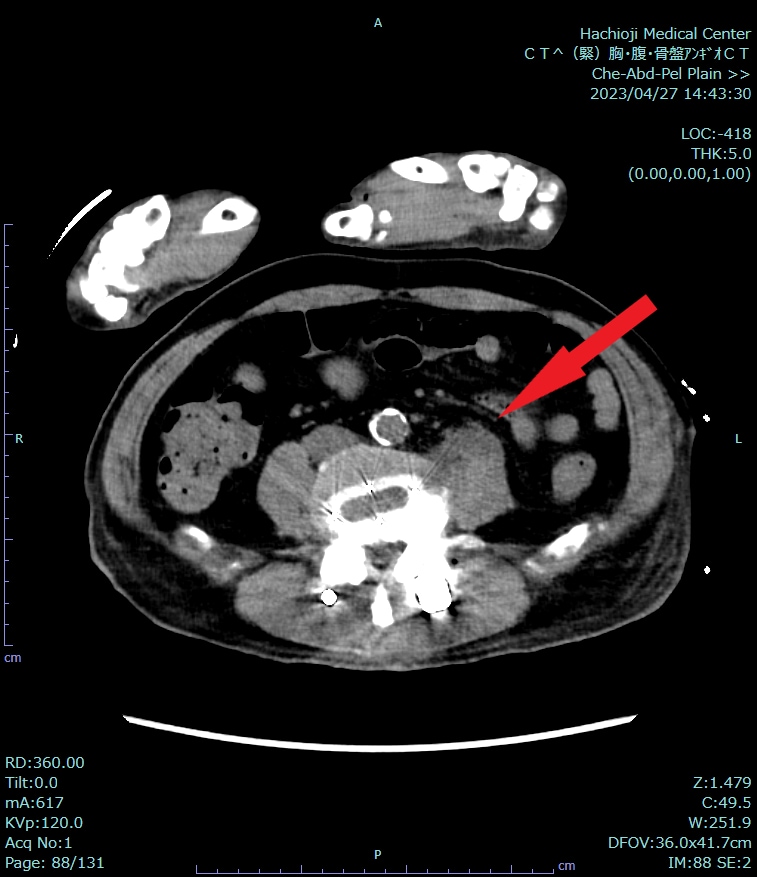

来院時には呼吸困難の他、CRP20mg/dlと炎症反応高値を認めていたため、熱源精査もかねて造影CTを施行した。炎症があれば血流が増加することから、炎症を生じている部位の増強効果がみられるため、異常所見が明瞭化する。特に膿瘍はある程度時間が経つと辺縁がよく造影される低吸収域がみられることが知られている。したがって、炎症反応が高く、腹腔内や骨盤腔内に炎症性疾患が疑われる場合は、造影CTによる熱源の検索が望まれる。本症例では、単純CTでは感染源の同定は困難であったが、造影することによって、右大腰筋に膿瘍があることがわかった。本症例のように、入院直後であり、情報が少ない場合はある程度すべての疾患も網羅できるように撮像する必要がある。ただし、単純CTに加え、造影CTでは動脈相と実質相の撮像を必要となり、被ばく量が増加するため、本当にその撮像が必要かはよく考えなければならない。

CT技術や撮像プロトコル設定について